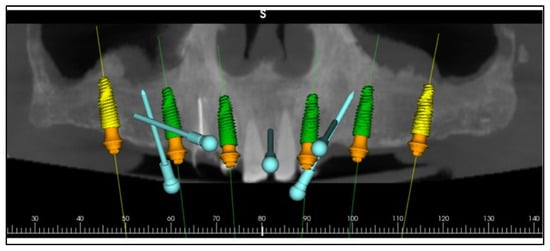

Comprehensive digital records were acquired, including intraoral scans, photographic series, and cone-beam computed tomography (CBCT). These were integrated into the RealGUIDE Universal Open System to create a virtual patient, enabling prosthetically driven planning based on facial analysis [,]. A digital smile design was constructed in Smilecloud to define the ideal tooth arrangement, vertical dimension, and smile curve [,,,,] (Figure 5, Figure 6 and Figure 7).

Figure 7.

Digital planning of the implants.

A stackable surgical guide system with magnetic retention was planned and fabricated. The guide set included a mucosa-supported base guide, an implant guide, and a multifunctional prosthetic verification guide. A flapless surgical approach was used. After base guide stabilization, the magnetic implant guide was sequentially positioned for each osteotomy. All six implants were placed according to the digital plan, achieving primary stability. Multi-unit abutments were installed to support immediate loading (Figure 8 and Figure 9).

Figure 8.

Planning of the surgical guide with magnetic retention using Real GUIDE Universal Open Systems.